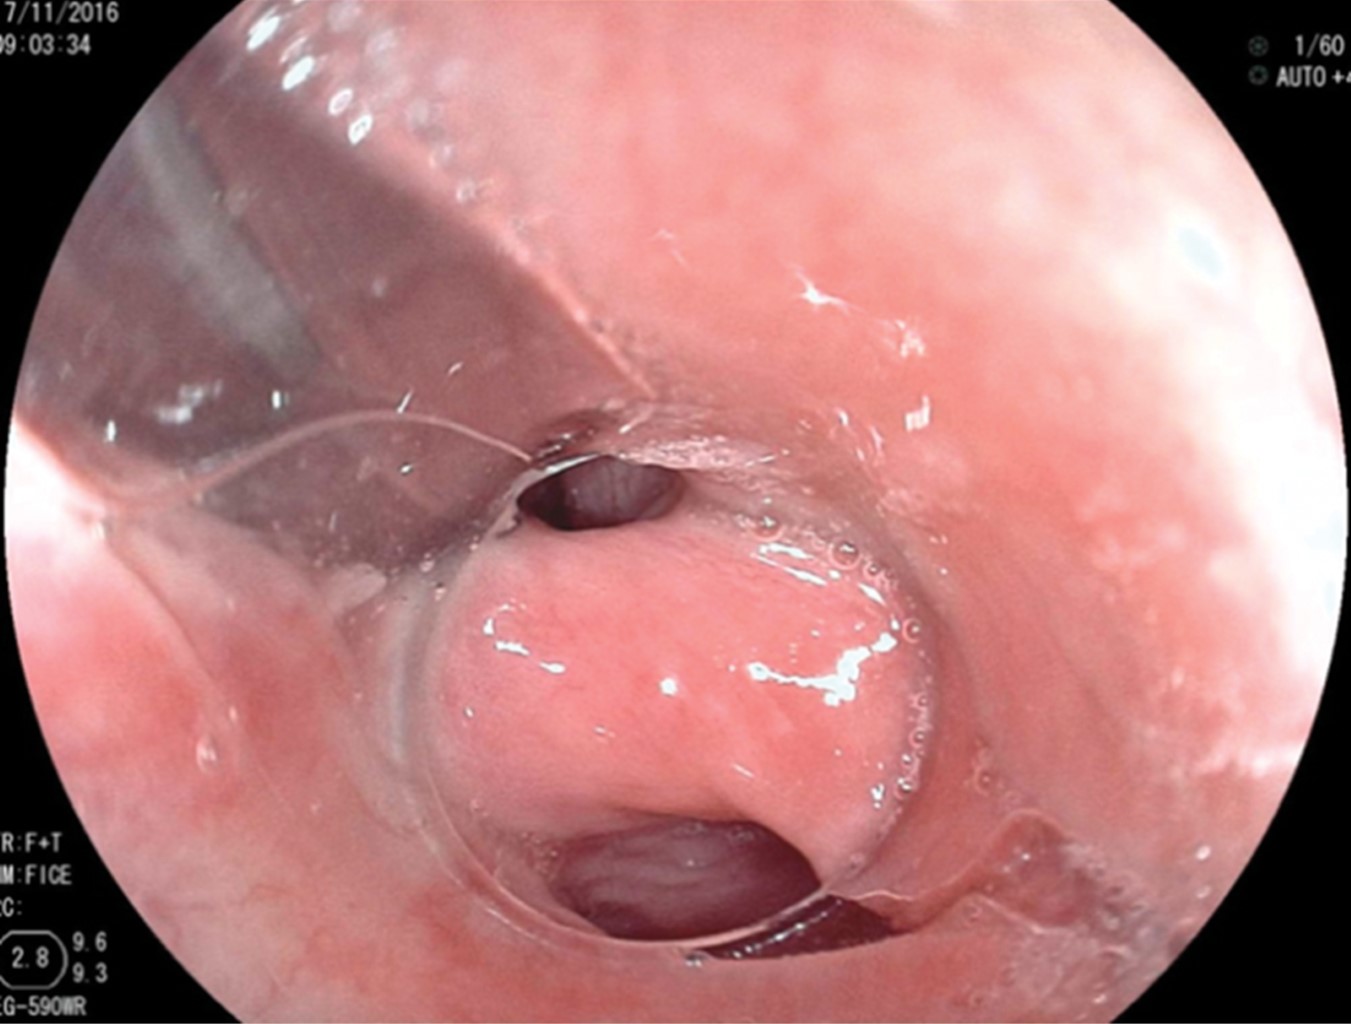

In the first 10 patients, once the esophageal lumen is identified, a metal guide is introduced and over it, a 7 mm or 21 Fr Savary-Gilliard dilator, which reaches the stomach and is left there. This adequately delimits the light of the diverticulum and esophagus (Figure 2). A clear plastic cap (MBL 6-1 Cook Endoscopy™) is placed at the distal end of the endoscope insertion tube and used as a spacer, which allows identification of the cricopharyngeal muscle septum. In the first 10 cases, an Olympus™ video gastroscope model GIF-H140 with an Olympus™ CV-140 image processor (Olympus Optical Co., Tokyo, Japan) of 9.8 mm diameter were used. Also, an Olympus UES-40 SurgMaster™ electrosurgical unit, and a needle knife (Needle Knife™, Cook Endoscopy, Winston-Salem, NC), were used. A cut was made in the edge of the esophageal light in the middle of the septum and towards the light of the diverticulum. First, the mucosa was cut exposing the cricopharyngeal muscle fibers (Figure 3). The cut was deepened until the section of the transverse fibers of the cricopharyngeal sphincter was completed, without necessarily reaching the bottom of the diverticulum (Figure 4), which allowed the edges of the mucosa incision to be brought closer together with metal clips, avoiding perforation and the risk of bleeding (Figure 5). The remaining four patients were treated with the POEM technique (Per Oral Endoscopic Myotomy), by infiltrating and lifting the submucosa with normal saline stained with methylene blue, then cutting the mucosa with the HybridKnife™ hydrodissector. The ERBE T-type™ is a multifunctional instrument that combines electrosurgical and waterjet technology in one. It lifts the mucosa and creates a submucosal tunnel, cutting only the transverse muscle fibers. Finally, the tunnel entrance was closed with endoscopic clips. In these patients, a Fujinon™ video gastroscope, Fujifilm Processor VP-4450HD™, ERBE VIO 200 D™ electrosurgical unit, and the ERBE HybridKnife, T-type™ with pure cutting and/or coagulation current (50 W) were used. Finally, the Savary-Gilliard dilator was removed. After the procedure, a swallow of water-soluble contrast material was given to rule out leakage. All patients were also given a single dose of antibiotics at the beginning of the procedure and were managed on an outpatient basis at home starting with a liquid diet after four hours.

Figure 2